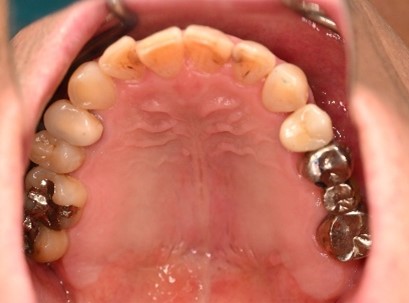

女性Cさん 60代(インプラント)

主訴

左下がぐらついて、噛むと痛い。歯がないところに以前部分入れ歯を入れたが、思うように使えなかったので、インプラントを入れたい。

治療内容

レントゲンで詳しく診てみると、左下の動いている歯、右下の一番奥は、保存することができず、抜歯しました。左下の抜歯したところは、骨造成後、左に2本、右に2本インプラントを埋入しました。

所感

左下の抜歯したところは、大きく骨が欠損していましたので、骨造成をしました。5か月間待ってからインプラントを埋入しました。骨をきちんと作ってから埋入して、正解でした。今回もX-Guideを使った埋入で、安心安全に行うことできました。

Before

赤丸は抜歯しました

【抜歯後】

【骨造成前】

【骨造成後】